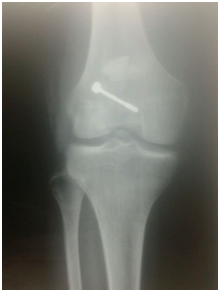

The tendon was sutured on itself by ethbound sutures, the side retinaculae was approximated and augmentation sutures was taken parallel to the tendon graft. The reconstruction was secured by stainless steel wire Figure 4 all circled around the patella and tibial tunnel. Release was done all sides of the knee to make knee flexion till 90 degrees. Closure in layers over suction drain and will padded pop back knee slab was done.

• Figure 4a & b Post operative plain X-ray.